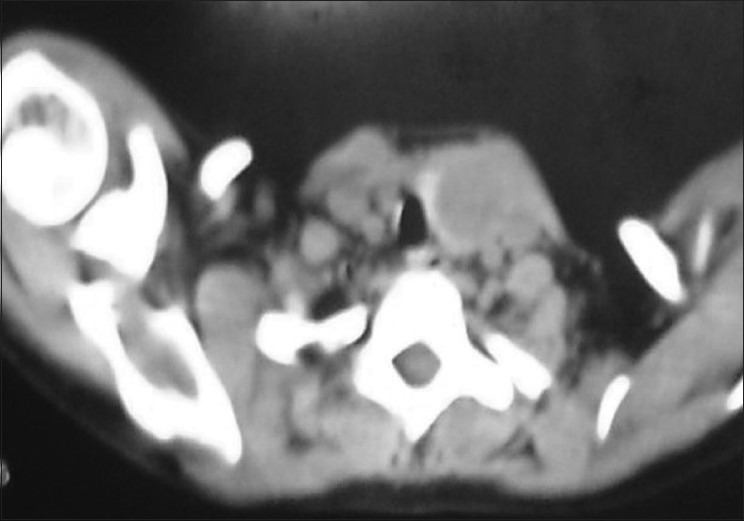

Apart from normal systemic findings and routine investigations, ultrasound of the swelling revealed a mixed solid and cystic swelling of 3 × 2 cm in the left lobe of the thyroid. Nuclear thyroid scan showed cold nodule [Figure 1]. Computerized tomography scan of neck also showed equivocal findings [Figure 2].

| Figure 2 Computerized tomography scan of the neck showing left thyroid nodule

Computerized tomography (CT) scan of the neck is useful to detect lesion less than 1 cm, to know the status of the nodes, to differentiate simple or complex nodular lesion. It also cannot define malignant or benign condition very reliably.[2]